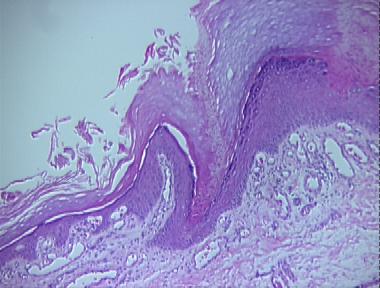

porokeratosis of Mibelli

Histologic Features